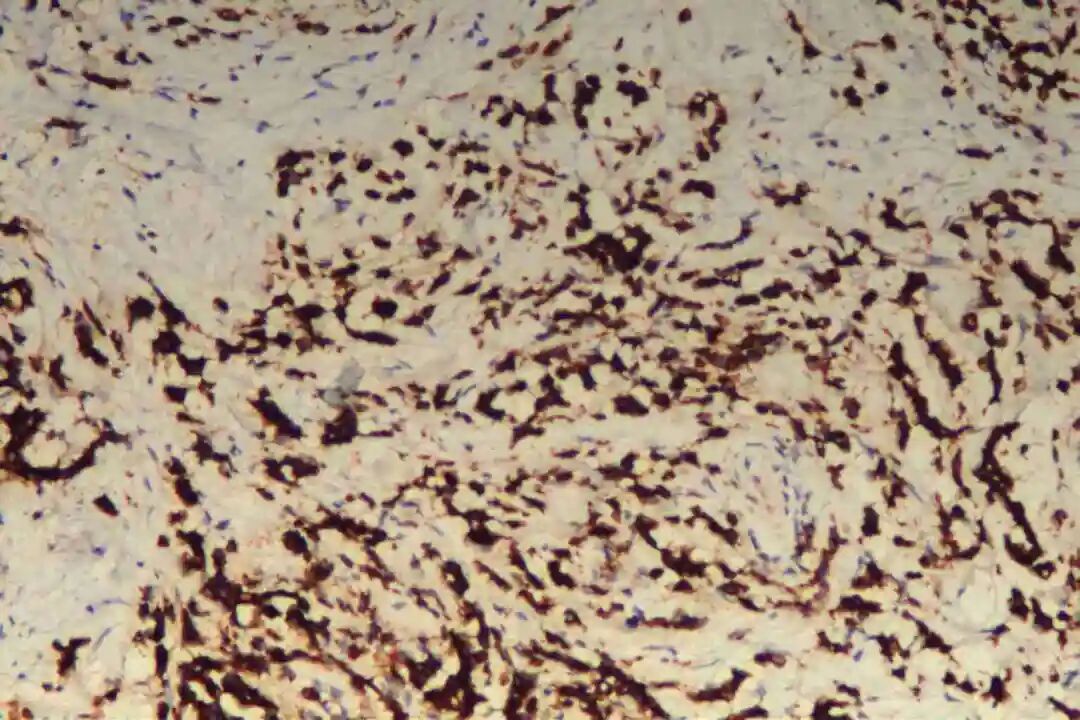

免疫组化:Her-2(0),P53(突变表型),CK20(+),CDX-2(+),SATB-2(-),Syn(+),INI-1(SMARCB1)(+),BRG1(SMARCA4)(+),Ki67(90%+),INSM1(灶+),CgA(-);

1.Syn(突触素):是神经内分泌细胞的特异性标志物,阳性提示肿瘤存在神经内分泌分化,即肿瘤细胞同时具备腺上皮分泌黏液与神经内分泌细胞分泌肽类激素的双重特征。

2. 免疫组化确认:Syn阳性是核心标志,常联合CgA(嗜铬粒蛋白A)、NSE(神经元特异性烯醇化酶)等提升神经内分泌分化检出率,同时需检测原发部位特异性标志物(如乳腺ER/PR/HER2、肺CK7/TTF - 1、胃肠道CK20/CDX - 2)以明确来源与分型。